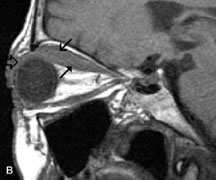

Extraocular muscle enlargement in patients with thyroid-associated orbitopathy is demonstrated equally well with CT and MRI studies. However, the superior tissue contrast on MR images reveals better details of the relationships of the optic nerve to the thickened muscles at the orbital apex (Fig. 16).50 In addition, MRI may be able to differentiate between muscles that are enlarged as a result of edema and active inflammation and those enlarged because of fibrosis by their T2 relaxation times.21 Quantitative MRI was not found to be accurate in predicting the success of low-dose orbital irradiation.51 However, a muscular index relating the diameters of the rectus muscles to the bony orbital dimensions was useful in predicting optic nerve compression.52

Fig. 16. A-C, T1-weighted MR scans obtained with a high-resolution surface coil demonstrate fusiform enlargement of the extraocular muscles. The medial, lateral, and inferior rectus muscles are especially involved. Note the relative sparing of the tendinous insertions, a finding characteristic of this disease process, as well as fatty infiltration of the lateral and inferior rectus muscles. There is marked proptosis, best visualized on the sagittal image (A), and mild crowding of the optic nerve at the orbital apex.